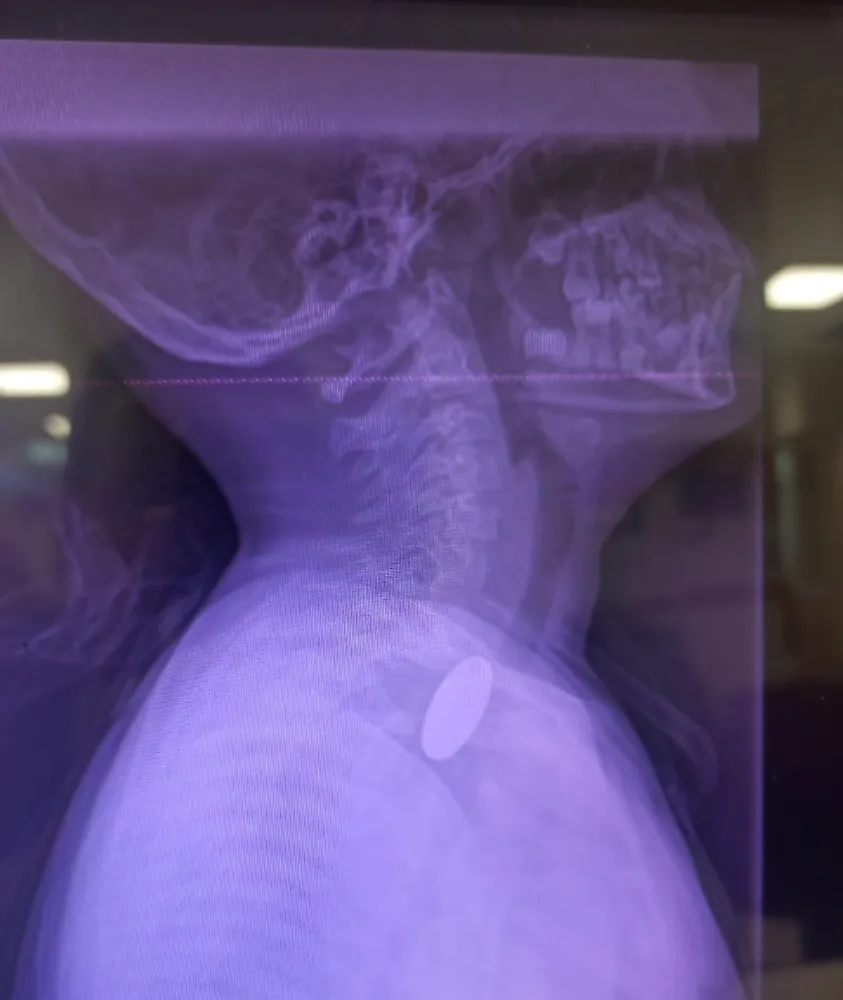

Edinilen bilgilere göre, yabancı cisim yutma şikâyetiyle hastaneye başvuran küçük hasta, yapılan ilk değerlendirme ve görüntüleme tetkiklerinin ardından ilgili branşlarca operasyona alındı. Yapılan incelemelerde, madeni paranın Y.K.’nin yemek borusuna kadar ilerlediği tespit edildi.

Madeni paranın çıkarılması için Gastroenteroloji Uzmanı Dr. Yaren Dirik ile Kulak Burun Boğaz (KBB) Hekimi Dr. Yasin Gökçınar tarafından ortak ve koordineli bir girişim gerçekleştirildi. Uzman ekiplerin titiz çalışması sonucu yabancı cisim, herhangi bir komplikasyona yol açmadan başarıyla çıkarıldı.

Konuya ilişkin açıklama yapan Siirt Eğitim ve Araştırma Hastanesi Başhekim Yardımcısı Dr. Burak Özkan, çocuklarda yabancı cisim yutma vakalarının ciddi riskler taşıdığına dikkat çekerek, “Hastanemize başvuran 8 yaşındaki hastamızın yemek borusuna kaçan madeni para, gastroenteroloji ve KBB ekiplerimizin koordineli çalışmasıyla sorunsuz şekilde çıkarılmıştır. Operasyon süreci başarılı geçmiş olup hastamızın genel durumu iyidir,” ifadelerini kullandı.